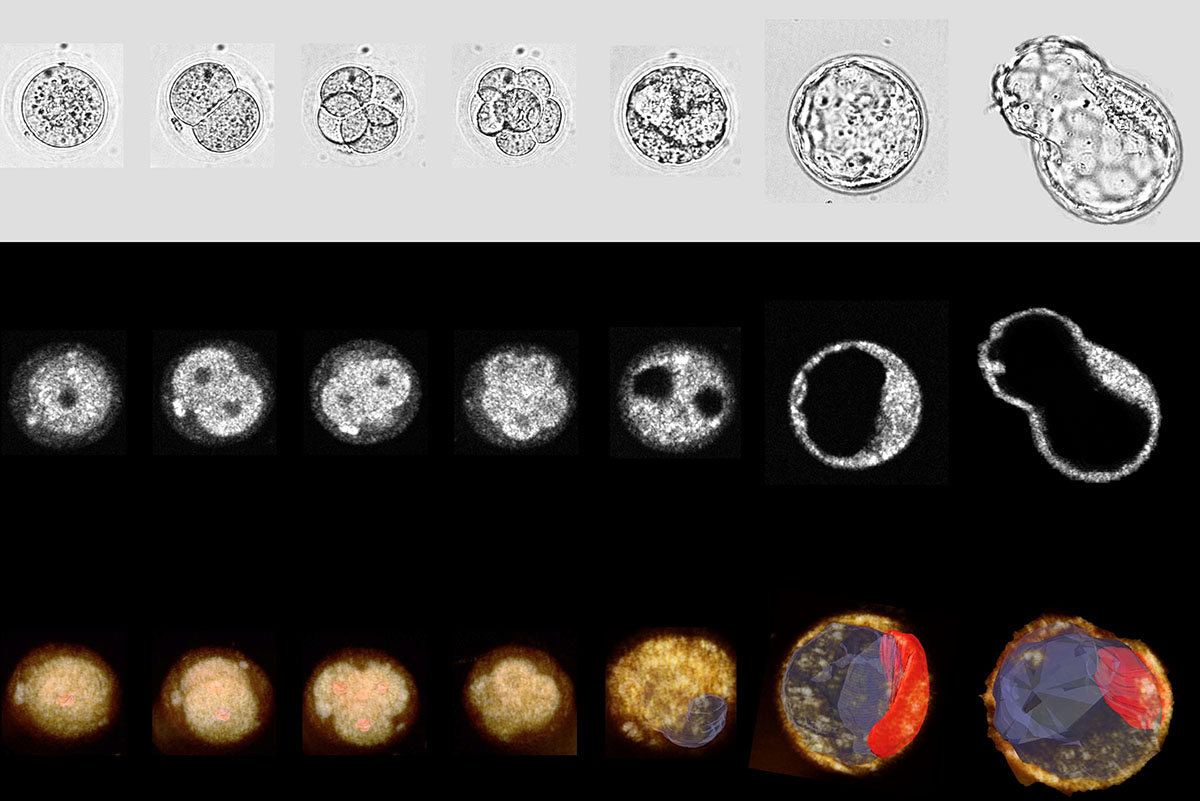

In vitro fertilization has served as the primary approach to tackle infertility for nearly fifty years, yet its live birth success rate remains below 40%. Choosing an embryo with the greatest potential might enhance the success rate, but current methods for capturing time-lapse images of developing embryos have been restricted.

A group of scientists from the McKelvey School of Engineering at Washington University in St. Louis employed dual-modality, 3D, time-lapse optical coherence microscopy (OCM) and brightfield (BF) imaging to observe mouse embryo growth and foresee successful blastocyst formation. Findings from this study, published in Communications Biology this spring, position OCM as a valid technique for selecting high-quality embryos for transfer and increasing the success rates of in vitro fertilization.